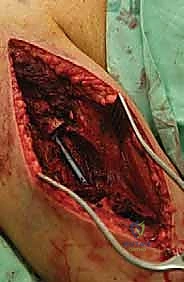

العزل العصبي الوعائي: هذه هي الخطوة الأهم. باستخدام أدوات الجراحة الميكروسكوبية ونظارات التكبير (Loupes)، يتم تحديد وعزل الأعصاب والأوعية الدموية وحمايتها بأشرطة ملونة.

استئصال الورم: يتم قص العظم بمنشار جراحي دقيق أعلى وأسفل الورم بمسافة أمان (Margin)، ويتم استخراج الكتلة الورمية بالكامل وإرسالها لمختبر الباثولوجي.

إعادة البناء الميكانيكي: يتم إدخال المكونات المعدنية (سواء مسمار نخاعي، شرائح، أو مفصل صناعي) وتثبيتها بقوة باستخدام الإسمنت العظمي إذا لزم الأمر. يتم التأكد من ثبات الهيكل الجديد تحت جهاز الأشعة السينية المباشر (C-arm).